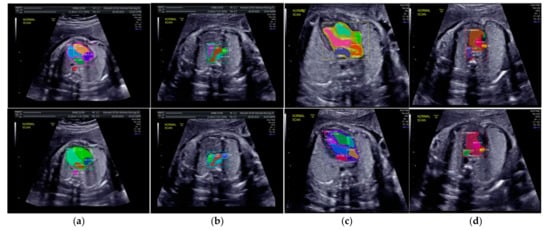

The IoU and DCS performance shows that the instance segmentation with the ResNet50 architecture as the backbone produced excellent predictions for all chambers in each view. Therefore, the Mask-RCNN with the ResNet50 architecture as the backbone of RPNs could segmented and detected the object based on the annotated RoI. In Figure 10a, the sample of segmentation result of fetal standard heart view is provided, and Figure 10b shows the heart chamber segmentation is presented separately. The standard view segmentation, to mark the shape of the cross sectional of the fetal heart, and the heart chambers segmentation, to show the part of each cross-sectional, belong here, whereas in Figure 11a–d, we experimented on two combinations, in such process a fetal heart view and heart chamber is merged, with about 17 heart chamber objects and four heart standard views to predict. Figure 11a,d shows the sample of segmentation results with different colors, but each object has the same description as Figure 10a,b. Based on the proposed model, all objects can be predicted with satisfactory performance (about 96.59% mAP, 79.97% IoU, and 89.70% DCS). The high mAP shows that the object detection process based on the proposed model obtained the overlapping area between the annotated and predicted RoIs of each bounding box close to 100%. The proposed Mask-RCNN model with ResNet50 yielded a 3.41% error in prediction between the annotated and predicted RoIs.

Figure 10.

The sample segmentation result of standard view and heart chamber for normal heart anatomy structure: (a) red color contour denotes the fetal heart boundary segmentation in each view, from left to right are 4CH, 3VT, LVOT, and RVOT; (b) heart chamber segmentation in each view from left to right are 4CH (red: RA, purple: LA, yellow: RV, and blue: LV), 3VT (green: DUCT, blue: AoA, and red: SVC), LVOT (green: LV, red: AoA, blue: RA, and yellow: RV), and RVOT (green: DUCT, cyan: MPA, red: AoA, and purple: SVC).

Figure 11.

Fetal heart view with heart chamber segmentation in (a) 4CH, (b) 3VT, (c) LVOT, and (d) RVOT for normal heart anatomy structure. Fetal heart view boundary and heart chamber part as the same description with Figure 10.